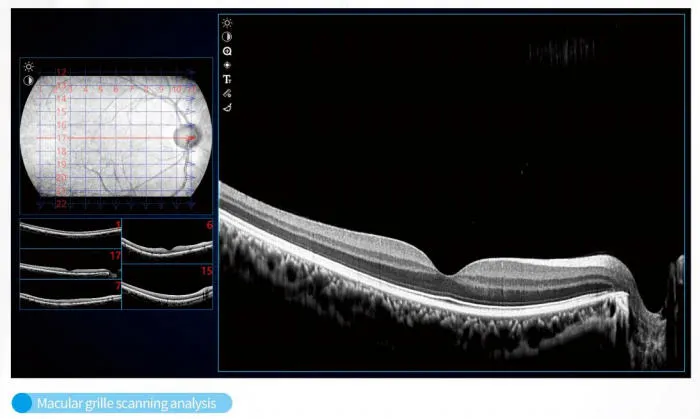

OCT Imaging Analysis

OCT Structural Scan

Diagnostic Interface

The C800 incorporates automatic eye-tracking, SLO scanning, and multi-mode tomographic imaging, ensuring stable visualization even for patients with difficulty maintaining fixation. Advanced choroidal thickness measurement and macular mapping support precise monitoring for myopia control, diabetic retinopathy, glaucoma, and age-related macular degeneration.

Built for intelligent healthcare, the system supports cloud-based data management, allowing remote consultation, multi-terminal data sharing, and seamless integration with hospital PACS systems. Its intuitive touch-screen interface enables faster examinations with minimal learning curve, making it suitable for both routine screening and advanced clinical use.

Retinal Analysis

Macular Mapping